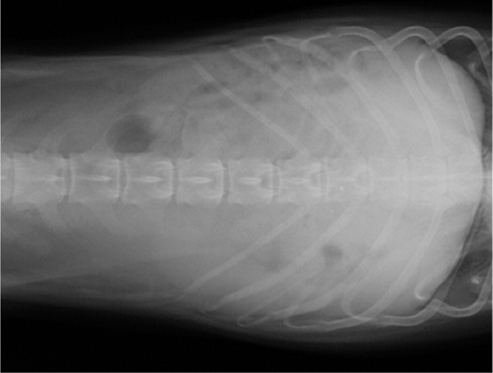

【画像診断】~ダックスフンド、雄10歳、グレート3の椎間板ヘルニア~

▲ダックスフンドのCT像、病変の部位は胸椎T11-12、白い部分(武蔵野動物CTセンターにて)